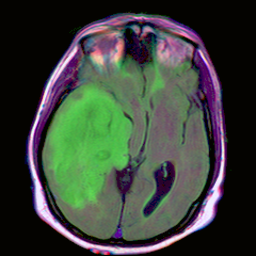

"description": "2D segmentation training and evaluation examples to identify and segment the brain based on Unet model given in https://pytorch.org/hub/mateuszbuda_brain-segmentation-pytorch_unet/",

Verify the result. The input image is on the left while the result is on the right.